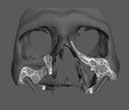

Az európai uniós rendeletekkel való harmonizáció keretében új szakvizsgák, feltételek, követelményrendszer alakult ki a hazai sztomatológiában. Megjelent az új orális implantológia szakvizsga, és egészen új szintre került a többi fogászati szakorvosi vizsga követelményrendszere is. Az új szakvizsgákhoz tartozó követelmények egyben a szakma új szabályainak is tekinthetőek, vagyis jelentős feladat elé állítják a rendelőket. A fejlődést a páciensek is nyomon követhetik az interneten keresztül, és ezzel új, és a réginél sokkal magasabb igényszintű fogászatot, implantológiát elvárásként fogalmazhatják meg. Ha ezt az új színvonalat, a fejlődést kevéssé követő fogorvosi rendelővel szemben várják el, akkor az ott végzett kezelések után kialakulhat a „konfliktus szituáció.” (1–3. képek)

Az implantológiában inkább a szájsebészeti jellegű témák voltak hangsúlyosak, a manuális eljárások dominanciája volt jellemző. Ma inkább a különleges csontpótlásokról, az előre megtervezett fogpótlásból (backwards planning = visszafelé tervezés) kiindult sebészeti tervezésről esik sok szó, ez vált követelménnyé. A digitális eljárások fölénybe kerültek a manuálisokkal szemben. A régi technológiák folyamatosan kikopnak a gyakorlatból. És itt is kérdés: Mi az, ami megfelel – még vagy már – a szakma szabályainak? Már csak emiatt is sok mindent újra kell gondolni (4–5. képek)